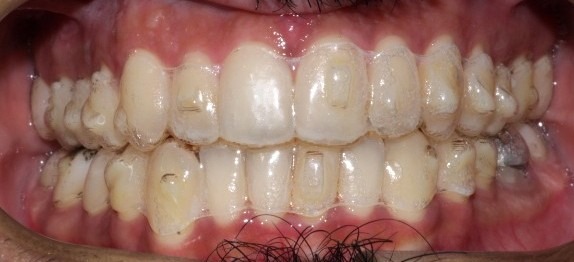

Before

During The Treatment

The patient had teeth crowding and a crossbite, where a lower tooth was biting in front of an upper tooth. This condition led to the accumulation of plaque, tartar, and cavities.